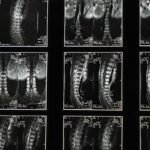

A quiropraxia é uma profissão da saúde que se dedica ao cuidado da coluna vertebral e do sistema nervoso. O princípio fundamental é que um corpo equilibrado e com a coluna alinhada tem maior capacidade de funcionar em seu potencial máximo. O profissional quiropraxista, através de avaliações detalhadas, identifica desalinhamentos, chamados de subluxações vertebrais, que podem comprometer a função nervosa e, consequentemente, afetar a saúde de diversas partes do corpo. O principal método de tratamento é o ajuste quiroprático, uma técnica manual e precisa aplicada nas articulações para restaurar o movimento e a função adequados.

Este tratamento quiroprático não se limita apenas à manipulação, mas envolve uma compreensão profunda da biomecânica do corpo e da relação entre a estrutura e a função. Os quiropraxistas utilizam as mãos para aplicar uma força controlada e específica nas articulações, buscando restaurar a mobilidade, reduzir a dor e permitir que o sistema nervoso funcione sem interferências. É uma abordagem não invasiva e que, para muitos, representa uma alternativa ou complemento importante aos tratamentos médicos convencionais.

O sistema nervoso é o centro de controle do seu corpo, responsável por coordenar todas as funções, desde o movimento até a digestão e a respiração. A coluna vertebral atua como uma armadura protetora para a medula espinhal, que é uma parte vital do sistema nervoso. Quando há desalinhamentos ou subluxações na coluna, essa proteção pode se tornar uma fonte de interferência, comprometendo a comunicação entre o cérebro e o resto do corpo.

É por isso que a quiropraxia enfatiza tanto a saúde da coluna. Ao otimizar o alinhamento vertebral, o tratamento quiroprático busca restaurar o fluxo nervoso sem impedimentos, permitindo que o corpo se autorregule e se cure de forma mais eficiente. Esta otimização não apenas alivia a dor nas costas e outros sintomas musculoesqueléticos, mas também pode ter um impacto positivo em funções orgânicas, no nível de energia e no bem-estar geral. É uma abordagem holística que reconhece a interconexão de todas as partes do corpo.